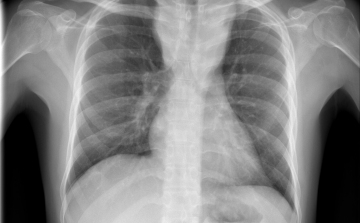

Egy líbiai menekülttáborból érkezhetett Európába a tbc egy új kórokozója

Menekültek révén, egy líbiai táborból érkezhetett Európába a tuberkulózis (tbc) kórokozójának egy korábban ismeretlen, gyógyszerekkel szemben ellenálló fajtája - írta a Die Welt című német lap a hírportálján szerdán.

Terjed a tbc Szatymazon?

Hétfő reggel óta tbc-tesztet végeznek el a gyerekeken egy szatymazi általános iskolában, ahol egy hete fertőző tüdőbetegségben halt meg egy korábban ott dolgozó nő - közölték az M1 aktuális csatorna déli Híradójában.

Csökkent a tbc-fertőzések száma Európában

Átlagosan 4,3 százalékkal csökkent az új tuberkulózisos (tbc-s) esetek száma 2010 és 2014 között az Egészségügyi Világszervezet (WHO) 53 országot magába foglaló európai régiójában.

Van miért aggódnunk

A tuberkulózis, a kanyaró, a HIV és a rezisztens baktériumok terjedése aggodalomra adhat okot Európában – állapították meg a régió járványügyi szervezetének (ECDC) éves jelentésében.

40 millió dohányos halhat meg tbc-ben 2050-ig

A kutatók szerint akár a 40 milliót is elérheti azoknak a dohányosoknak a száma, akik 2050-ig tuberkulózisban (tbc) veszítik életüket.